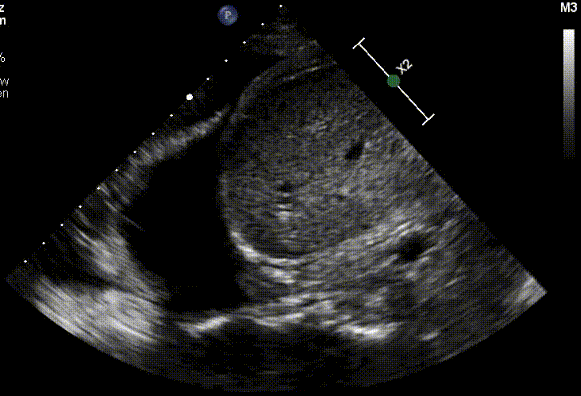

I klinikken finder man det typisk som den der tilsløring af sini på røntgen af thorax eller væsken samme sted på ultralyd. Her er et eksempel på en pleuraeffusion i højre side over leveren. Snuppet fra den rigtig gode side showmethepocus.com under CC BY-NC 4.0.

Med tilladelse fra showmethepocus.com. Link til kilden og licens ovenfor.

Man ser en atelektatisk lunge til venstre, der flapper rundt i sort væske midtfor, diaphragma og leveren til højre. Helt i bunden af billedet ses columna, som man ellers normalt ikke kan se.